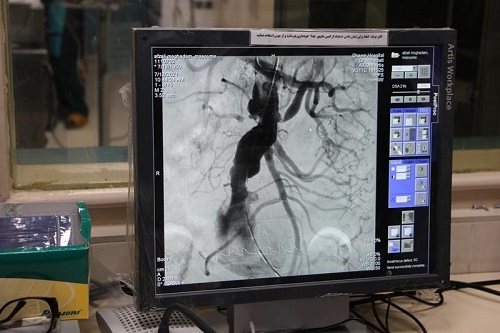

دکتر غلامحسین کاظم‌زاده در گفتگو با وبدا، ضمن اشاره به انجام دومین عمل جراحی داخل عروقی آئورت شکمی( Evar ) در بخش جراحی اندوواسکولار بیمارستان ولایت گفت: بیمار تحت عمل جراحی، در پی آنورمیسم یا اتصاع شریان آئورت شکمی که به میزان قابل توجهی ریسک پارگی شریان را افزایش می دهد، کاندید عمل جراحی قرار گرفت و با توجه به بالا بودن سن بیمار و مشکلاتی که جراحی باز به لحاظ بیهوشی و ICU پس از عمل جراحی می تواند برای بیمار ایجاد کند، یکی از گزینه‌های انتخابی ما استفاده از شیوه جراحی اندوواسکولار بود که طی آن از داخل رگی در قسمت کشاله ران و شریان‌های فمورال، وسیله‌ای در داخل شریان آئورت قرار می‌ گیرد تا آنوریسم را همانند یک آستر از داخل بپوشاند.

وی ادامه داد: عمل جراحی داخل عروقی آئورت شکمی که اختصاراً EVAR  نامیده میشود، سال‌هاست که در دانشگاه علوم پزشکی مشهد بکار گرفته شده، اما در بیمارستان ولایت برای دومین بار از این شیوه  استفاده می شود و هر چند هزینه های آن قابل توجه است، ولی نسبت عمل جراحی باز خطرات کمتری دارد.

یادآور میشود: جراحی آنوریسم آئورت شکمی در چند سال اخیر در ایران، با کمک روش های اندووسکولار و با استفاده از دستگاه ˈآنژیوگرافیˈو کارگزاری ˈاستنت گرافت آماده شدهˈبرای جایگزینی آئورت در اتاق عمل هیبرید انجام می شود. مزیت این نوع ترمیم آن است که نیاز به جراحی شکمی وجود ندارد و بنابراین این روش نسبت به روش سنتی ایمن تر است و بیمار زمان کمتری را در بیمارستان می گذراند.